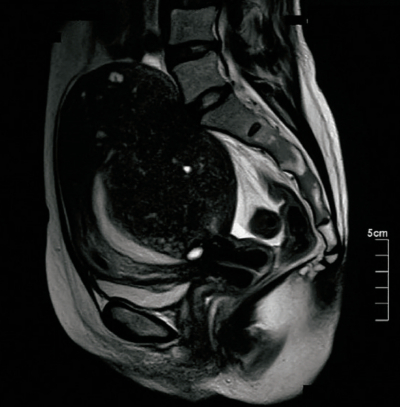

内診で子宮は 15 cmに腫大し硬く、可動性は良好である。付属器は触知しない。

血液所見:赤血球 340 万、Hb 9.0 g/dL、Ht 28%、白血球 4,100、血小板 23万。骨盤部単純MRIのT2強調矢状断像を別に示す。